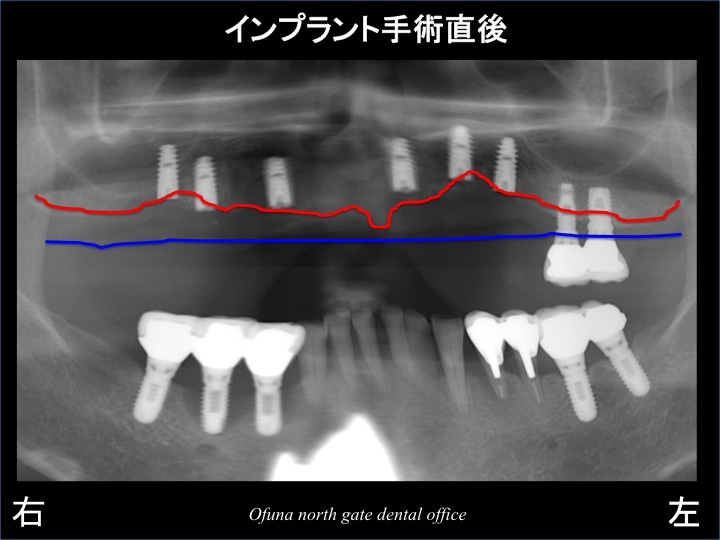

以下のレントゲンは、インプラント手術直後です。

以下のレントゲンは、先程のインプラント手術直後のレントゲンに骨吸収の状態を書いたものです。

骨吸収に沿ってインプラントが埋入されているのが分かると思います。

手術直後のレントゲンだけをみると簡単そうに思えますが、結構大変なのです。